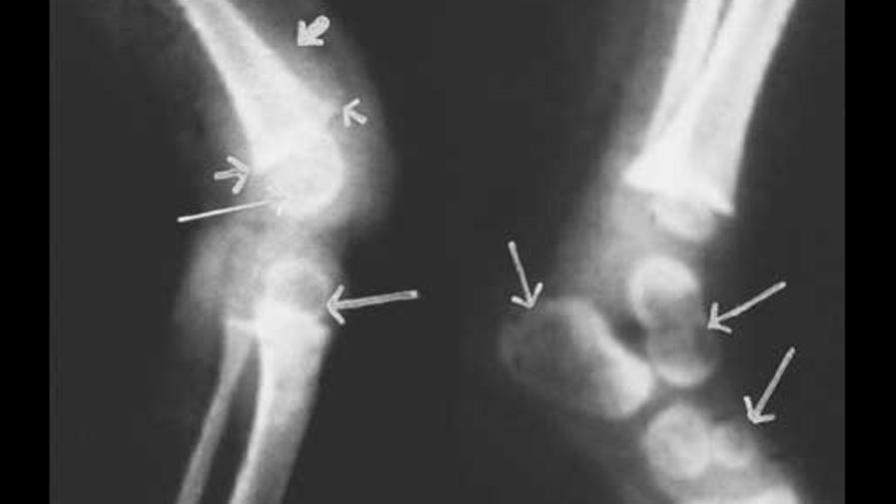

"Es muy sorprendente ver esto", dijo el doctor Mitch Blair, del Colegio Real de Pediatras y Salud Infantil. "Los niños llegan con piernas arqueadas, muñecas hinchadas y en ocasiones costillas hinchadas", indicó. "Esto no es algo que deberíamos ver porque es completamente prevenible". Agregó que ese estado es reversible en cuanto los niños comienzan a recibir suficiente vitamina D, generalmente en tabletas o inyecciones.